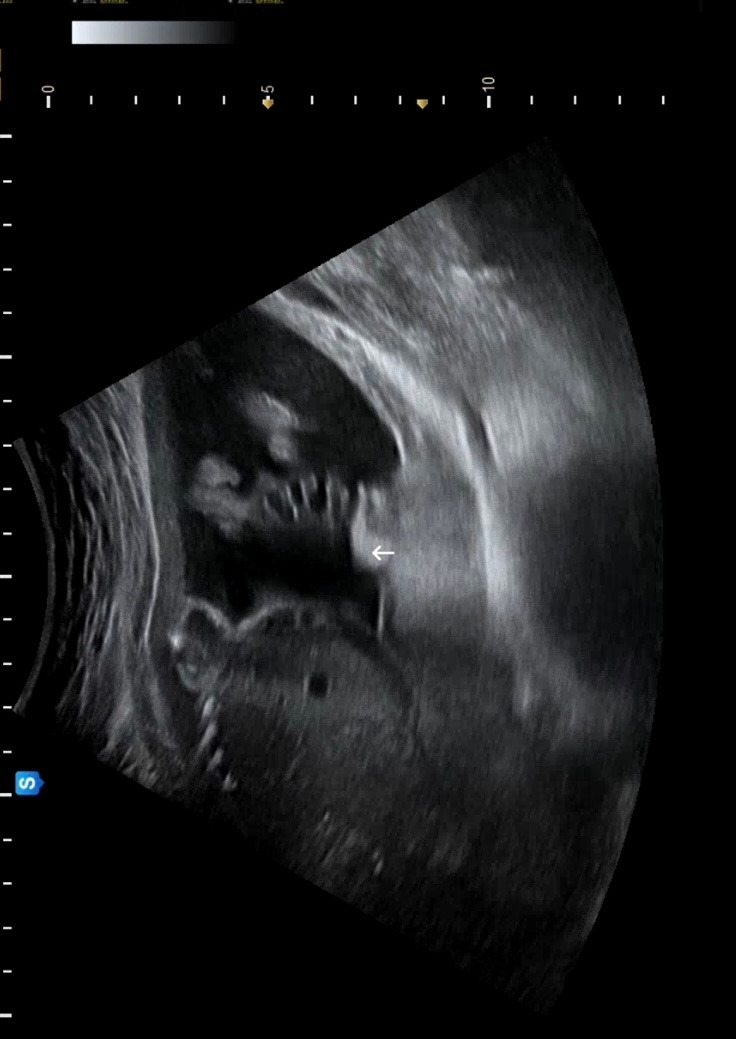

21주차 우리 애기. 왼쪽이 눈 오른쪽이 코랑 입이다. 벌린 입이 너무너무 귀여워서 이 영상을 캡쳐해 여러 번 돌려봤다. 남편은 봐도 잘 모르겠다고 한다(왠지 서운 ㅠ) 그래도 엄마 눈엔 다 보여 빵빵아‪‪‬‪‪‬